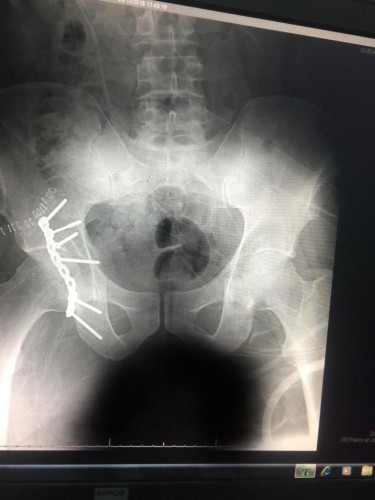

دخل على أثرها المستشفى لتلقي العلاج وعلى الفور قام الفريق الطبي بإجراء عملية عاجلة لعلاج الكسور ، حيث كانت الإصابة خلع ورك أيمن مع كسر خلفي مفتت في الجوف المفصلي للورك الأيمن .

وقد تم ولله الحمد التثبيت الجراحي بشريحة إعادة بناء مع براغي مقفلة ، علماً أنها من العمليات الكبيرة التي يتم إجرائها بالمستشفيات التخصصية الكبرى حيث تم إجرائها بمستشفى القريات العام